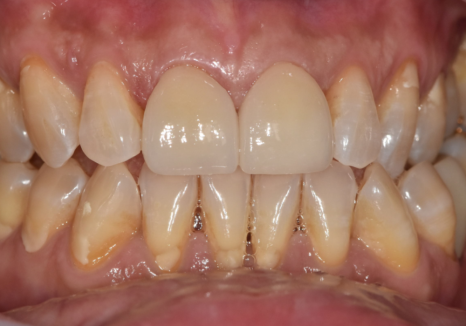

누런 이, 나이가 들수록 치아가

점점 더 누렇게 변하는 이유

고덕동 치과 누런 이, 앞니 사이 틈, 잘못된 관리 때문일까?

환자분의 또 다른 고민은

치아 색상이 예전보다

어둡고 누렇게 보인다는 점이었습니다.

250318

우리 치아는

겉을 감싸는 하얀 법랑질(enamel)과

그 안쪽의 노란빛을 띄는 상아질(dentin)로

이루어져 있습니다.

법랑질은 우리 몸에서

가장 단단한 조직이지만,

평생 수천 번의 저작 운동과

음식, 생활 습관, 외부 자극을 반복적으로 받으며

조금씩 마모될 수밖에 없습니다.

이 과정에서

법랑질의 두께가 얇아지면

안쪽의 상아질 색이 비쳐 보이게 되고,

치아는 점점

어둡고 누렇게 보이게 됩니다.

이처럼 노화로 인한 치아 변색은

표면 착색과는 원인이 다르기 때문에

전문가 치아미백만으로는

개선이 어려운 경우가 많습니다.